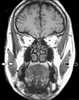

Hemiatrophy

Parry–Romberg syndrome (PRS) is a rare disease characterized by progressive shrinkage and degeneration of the tissues beneath the skin, usually on only one side of the face (hemifacial atrophy) but occasionally extending to other parts of the body. An autoimmune mechanism is suspected, and the syndrome may be a variant of localized scleroderma, but the precise cause and pathogenesis of this acquired disorder remains unknown. [Source: Wikipedia ]